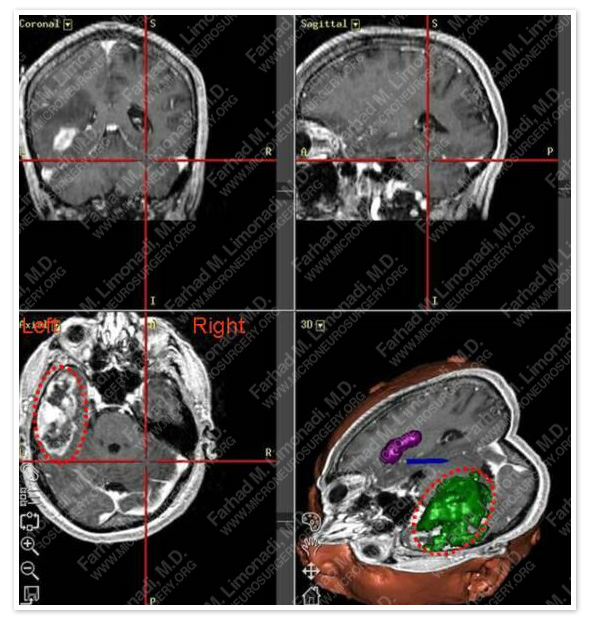

Computer Navigation

Volumetric map of tumor together with neurophysiological cortical mapping assisted in safe and subtotal resection of the tumor while safeguarding vital neurovascular structures.